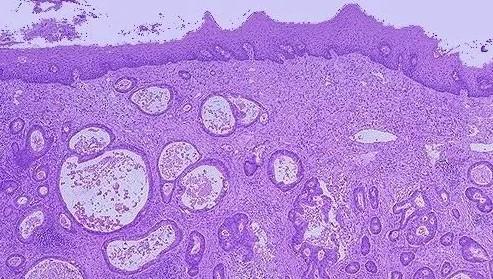

最终患者的病理分析结果提示:患者患有胃底低分化腺癌 , 伴部分印戒细胞癌 。 这类肿瘤恶性程度非常高 , 本来几乎被判了死刑 , 但在医生和病人共同的努力下终于绝处逢生 , 打出了漂亮的配合!